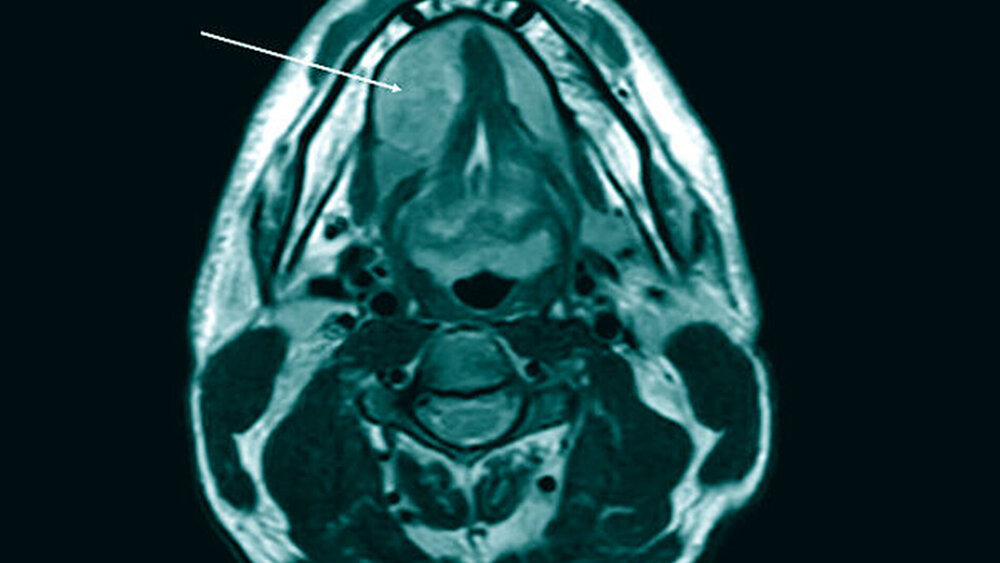

Zur weiteren Diagnostik erfolgte eine Magnetresonanztomografie (MRT). Diese zeigte eine glatt begrenzte, heterogene Raumforderung der Glandula sublingualis rechts (33 mm x 31 mm x 20 mm) mit Verdrängung der umgebenden Strukturen ohne Infiltration (Abbildungen 1 und 2). Es wurde die Verdachtsdiagnose eines pleomorphen Adenoms der Glandula sublingualis rechts gestellt. Weiterhin wurde eine deutlich atrophierte Glandula submandibularis rechts beschrieben.